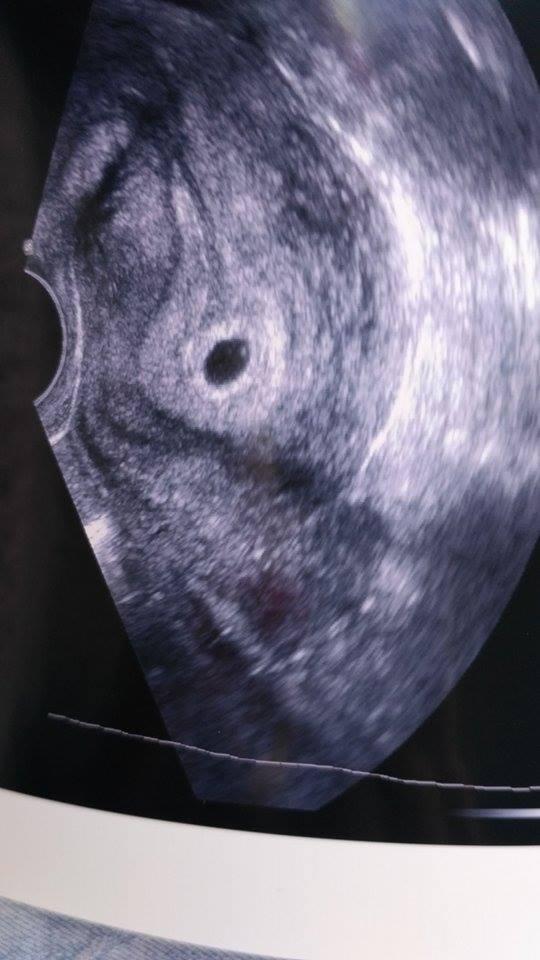

@tornadolu v neděli 22.1.vysazuji prášky budu cekat na MS a pak se hned musim objednat na gindu az po Ms jesi me vyrostla sliznice beru to 3 měsíc tak jsem zvědavá no nějaká smutná jsem znáš to...😢